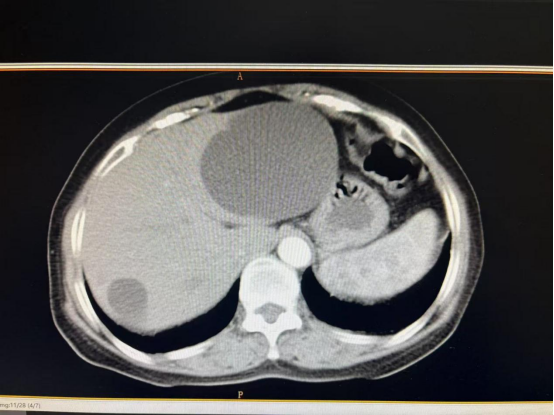

患者徐女士在老家体检时发现肝脏存在直径达9cm的囊肿,同时甲状腺超声提示4A类钙化结节(恶性风险约5-10%)。面对两地医院均建议限期手术的情况,患者因担忧多次手术风险及经济压力陷入两难。我院外一科团队接诊后,经与总院普外科段飞主任会诊评估,创新性提出"甲状腺癌根治术+腹腔镜下肝囊肿开窗引流术"联合术式方案。

医疗团队特别设计了"先颈部后腹部"的手术路径。术中快速冰冻病理确诊为甲状腺乳头状癌后,立即实施中央区淋巴结清扫,随后无缝衔接进行腹腔镜微创肝囊肿处理。整个手术历时2小时,出血量控制在10ml以内。